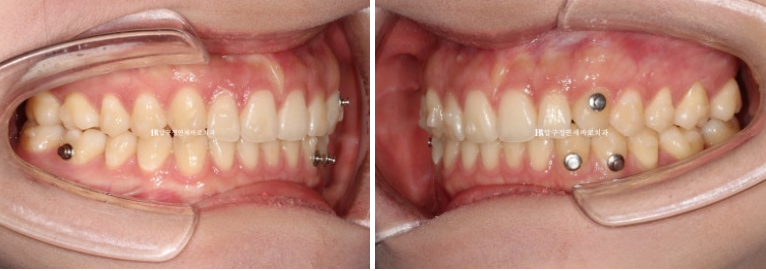

위 아래 중심선이 약 2mm 차이가 나는 상태이고 측절치와 송곳니에 덧니도 보입니다.

24.02

옆에서 보면 가운데 앞니 세개가 뒤로 기울어져 있는 것이 보입니다.

우측은 교합관계가 II급입니다.

앞니 세개가 입천장쪽으로 들어가 있습니다.